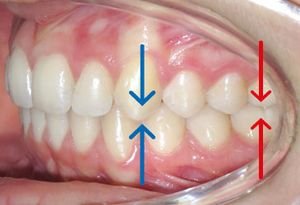

Position de la Première Molaire Supérieure : Analyse 6-PTV

La position de la première molaire supérieure est évaluée par la distance entre le point le plus distal de cette dent et le bord postérieur de la fente ptérygo-maxillaire (axe ptérygoïdien vertical, PTV).

Formule de référence : 6-PTV ≈ âge du patient + 3 mm ± 3 mm

Exemples d’application :

- Patient de 10 ans : 6-PTV devrait être d’environ 13 mm (10+3)

- Patient de 12 ans : 6-PTV devrait être d’environ 15 mm (12+3)

- Patient de 15 ans : 6-PTV devrait être d’environ 18 mm (15+3)

Intérêt clinique :

Cette mesure permet de :

- Prévoir dans quelle mesure on peut distaliser la molaire supérieure

- Déterminer si la malocclusion est due à une malposition molaire supérieure ou inférieure

- Planifier la nécessité d’extractions ou de dispositifs de distalisation

- Évaluer l’espace disponible en arrière des molaires

Si la valeur mesurée est inférieure à la norme, cela indique que la molaire est trop mésialée et qu’il existe peu d’espace pour la distaliser. Inversement, une valeur supérieure suggère que la molaire est déjà distale et qu’un espace de distalisation existe.